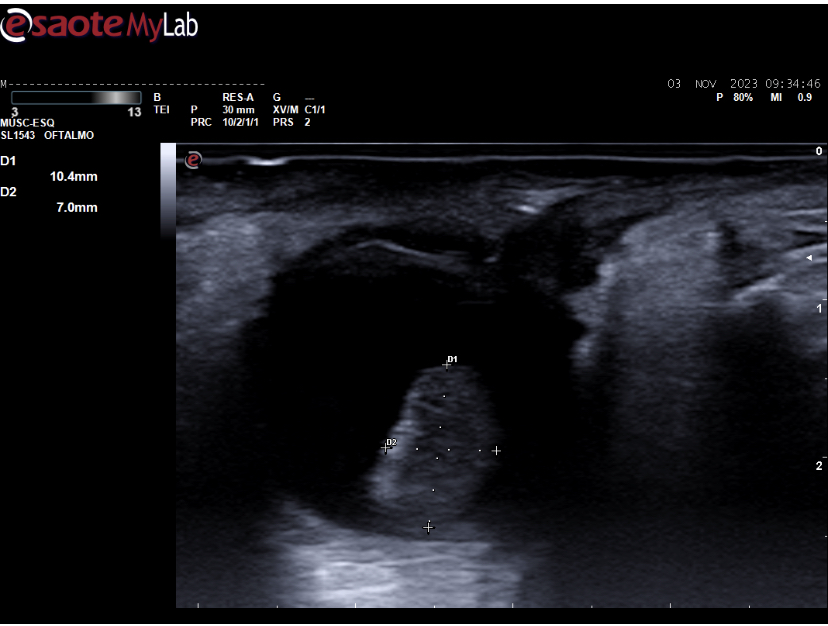

Ecografía ocular: lesión sólida polipoidea homogénea de 10*6 mm vascularizada junto a imagen de membranas hiperecoicas avasculares y móviles con los movimientos oculares en polo posterior.

Se deriva a urgencias oftálmicas hospitalarias donde corroboran nuestras imágenes con otra ecografía realizada por servicio de radiodiagnóstico y completan estudio con RMN: lesión coroidea hiperintensa en T1 e hipointensa en T2 de medidas basales de 16 mm por espesor de 6 mm con desprendimiento de retina posteroinferior y pequeño foco de hemorragia subretiniana posterior.